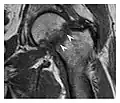

The greater tuberosity of the humerus is also an illustrative location of occult fractures. The osseous injury may follow seizures, glenohumeral dislocation, forced abduction, or direct impaction. They are commonly discovered on MRI in symptomatic patients with suspicion of rotator cuff tear. Coronal images are best suited for detection. They appear as crescentic oblique lines surrounded by a bone marrow edema pattern (Figure 5). The rotator cuff must be inspected since associated ligamentous lesions are common. In the ankle, malleoli and tarsal bones should be checked carefully for any cortical disruptions and radiolucent lines that may reveal a fracture. Awareness of the exact location of the pain will help direct the attention of the interpreter when searching for very subtle signs of fracture (Figure 6).[1]

-

a -

b

Figure 6: Subtle anterior talar fracture in a 39-year-old man presenting with ankle pain after a fall. (a) Anteroposterior radiograph shows a subtle oblique radiolucent line through the talus (white arrows). (b) Sagittal CT reformation confirms the presence of an anterior talar fracture with cortical offset (black arrow). Avulsion fractures, which consist of a detached bone fragment resulting from a ligament or tendon pulling away from the bone, may also present with subtle radiographic signs. Tiny osseous fragments near the presumed attachment site of a ligament suggest this diagnosis. Common sites are the lateral tibial plateau (the Segond fracture), the spinal tuberosity of the tibia resulting from anterior cruciate ligament avulsion, and the ischial tuberosity.[1]